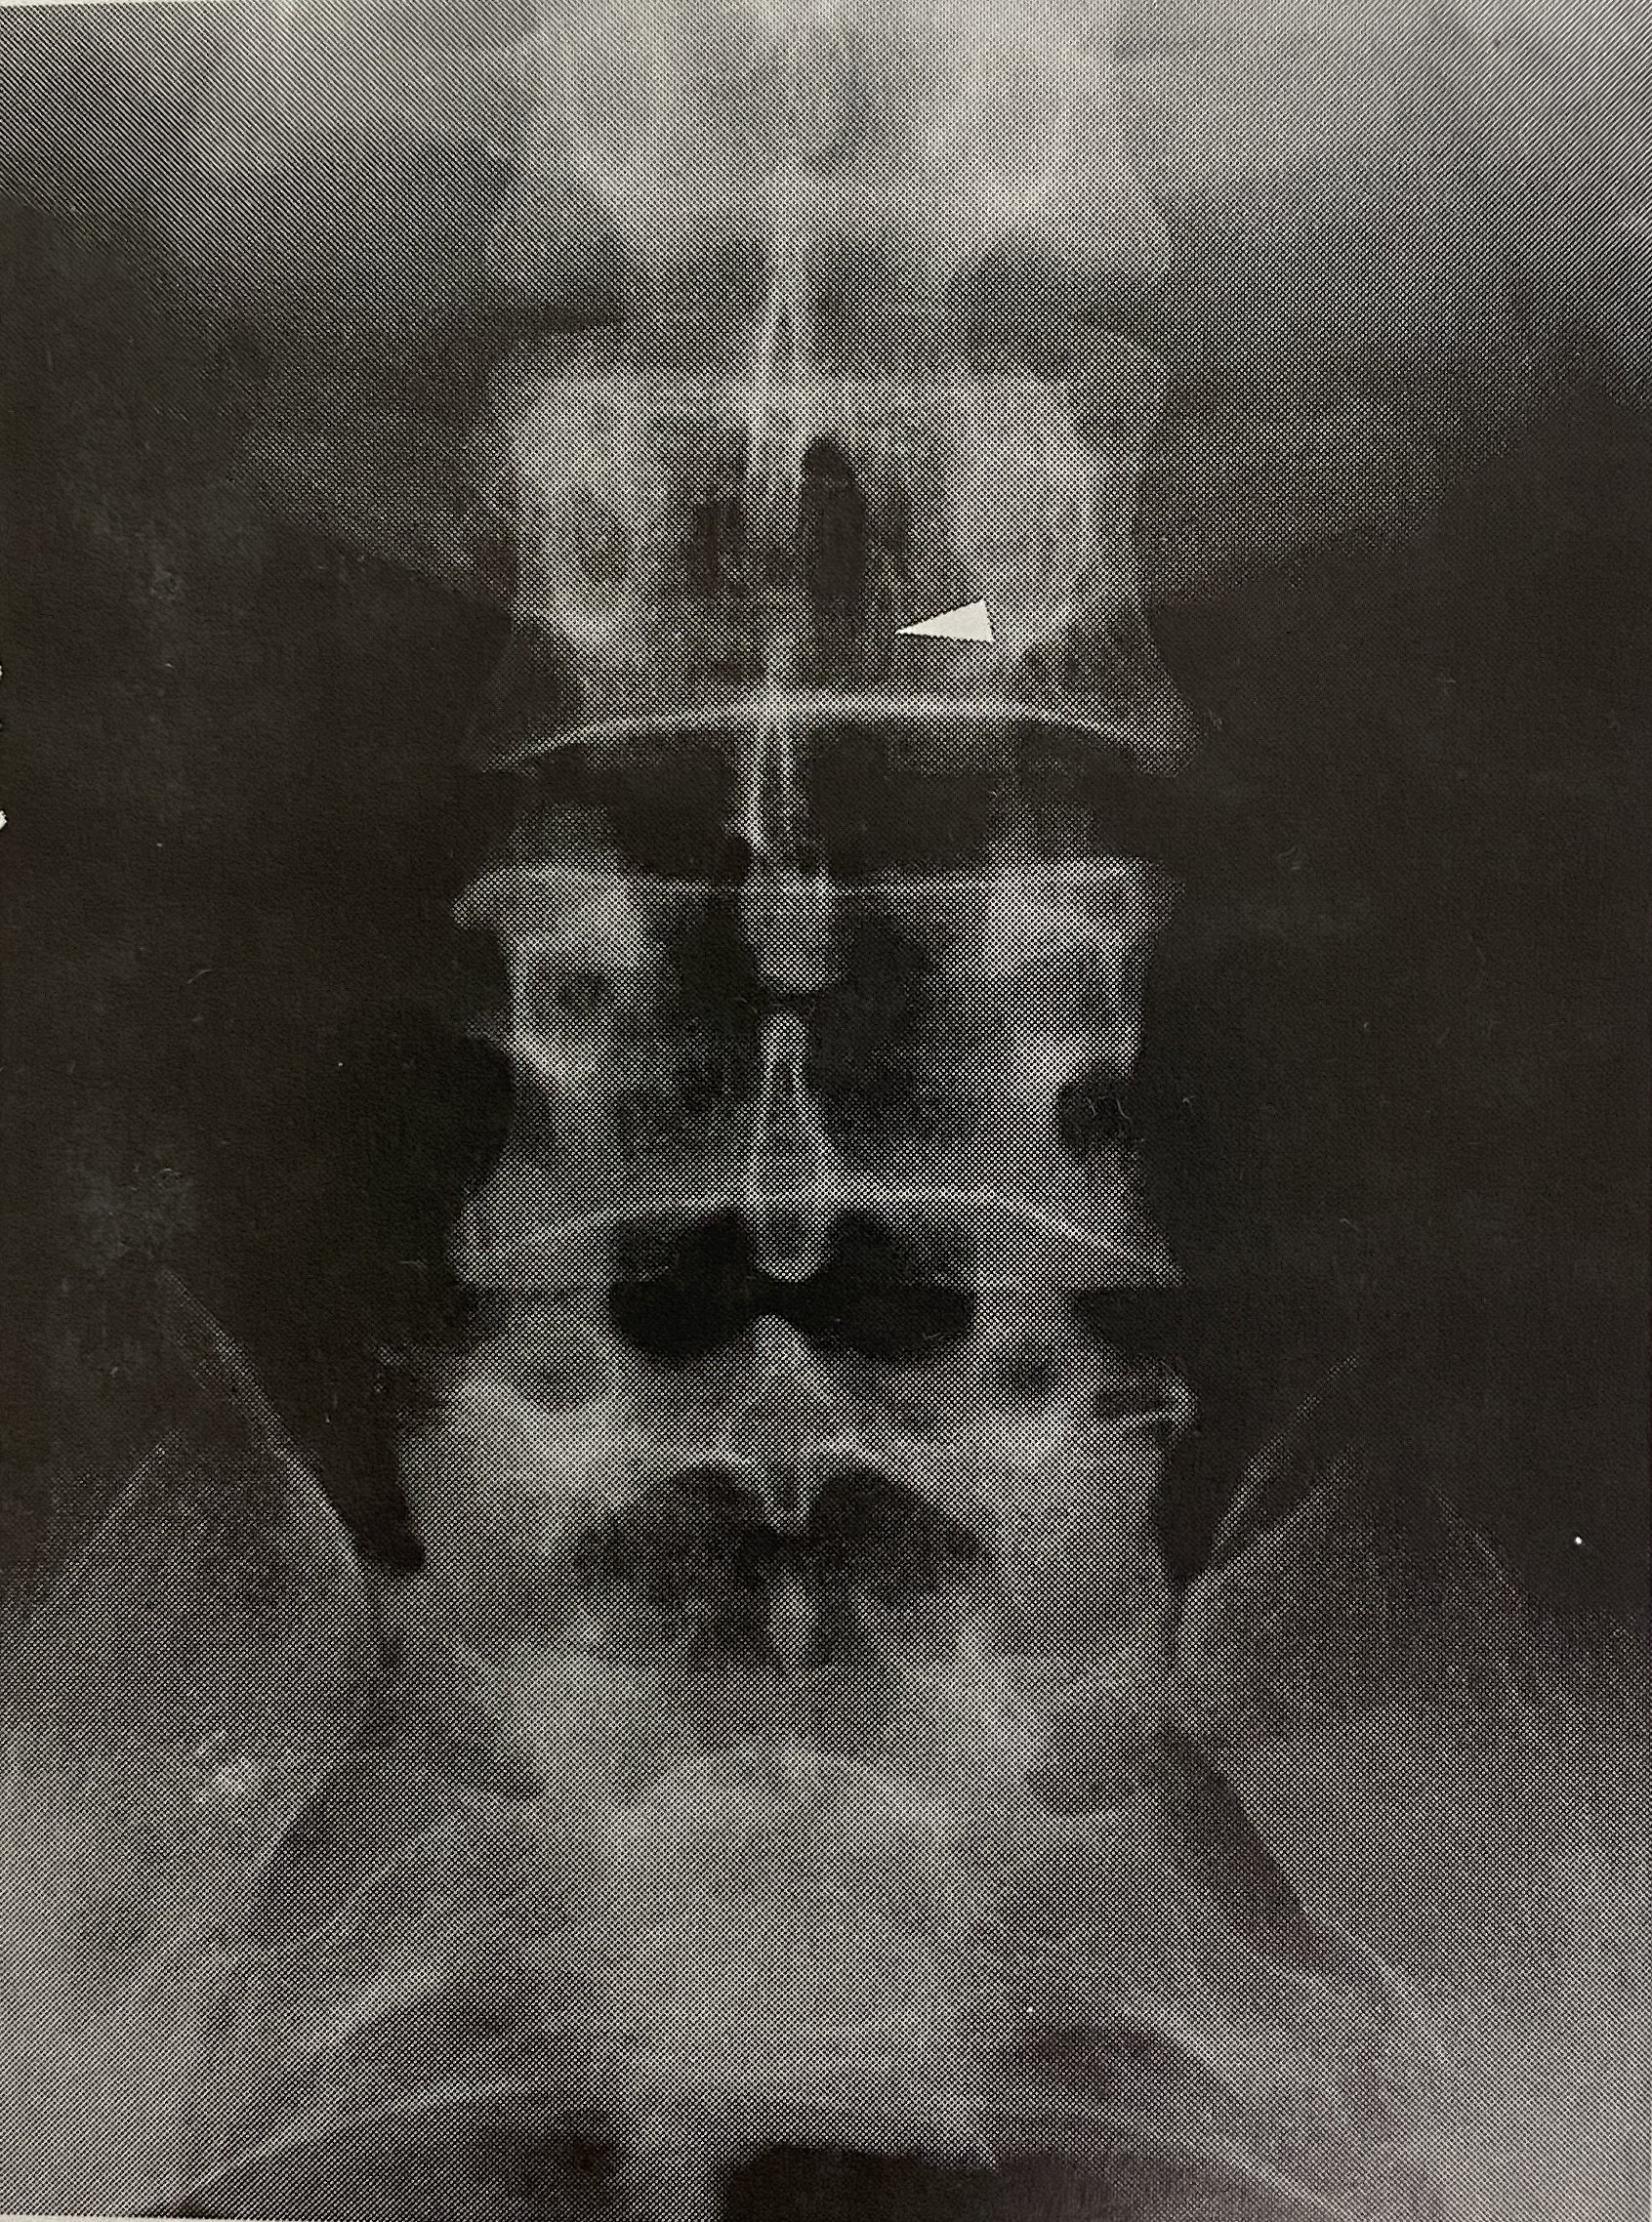

本次胸椎多发骨折,同时有椎体血管瘤

图片尺寸2000x2667